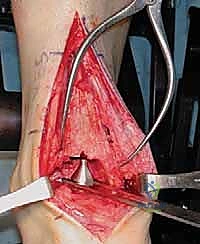

2. الوصول الجراحي الدقيق

يقوم الدكتور هطيف بعمل شق جراحي دقيق في الجزء الأمامي من الكاحل. بفضل خبرته في الجراحة الميكروسكوبية، يتم إبعاد الأوتار والأعصاب والأوعية الدموية بحذر شديد لحمايتها من أي ضرر.